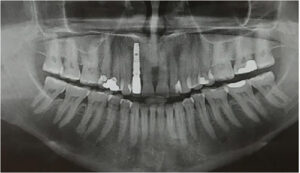

Після того, як виключені всі протипоказання, проводяться стандартні для всіх хірургічних втручань лабораторні дослідження – загальноклінічний і біохімічний аналіз крові, визначаються показники згортання крові, а також аналізи на ВІЛ-інфекцію, гепатит В і С, сифіліс. З інструментальних методів дослідження використовується рентгенографія (ортопантомограмма – панорамний знімок зубів), при необхідності – КТ або МРТ верхньої і нижньої щелепи.